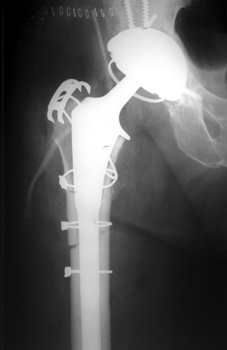

Control perforation lateral femoral cortex, reduced by cerclage cables. A control perforation of the lateral femoral cortex was performed in this revision total hip replacement to facilitate removal of the old femoral prosthesis. It is reduced by cerclage cables.

Vascular channel. Linear lucency seen on pre and post operative frog views is vascular channel. These are seen best on the frog leg view, entering the femoral cortex distally and traveling proximally toward the hip into the marrow space.